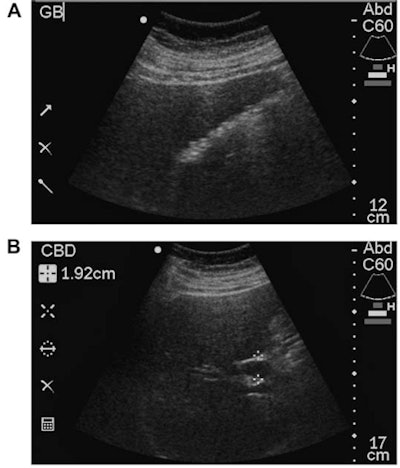

The conventional ultrasound studies were performed by sonographers certified by the American Registry for Diagnostic Medical Sonographers (ARDMS) on an HD-5000 (Philips Healthcare), IU-22 (Philips), E-8 (GE Healthcare), or Antares (Siemens Healthineers) scanner. The study's senior author, Dr. Robert Harris, read the exams immediately after they were performed; these interpretations served as the reference diagnostic standard and were confirmed or modified one year after patient enrollment based on further clinical evaluation and follow-up, laboratory/pathologic data, and additional imaging studies. Harris, who has 23 years of general ultrasound experience and 10 years of compact ultrasound experience, then performed all point-of-care ultrasound studies using a SonoSite 180 Plus scanner (Fujifilm SonoSite). The point-of-care exams were targeted, focused exams that took two to three minutes to perform.

High image-quality scores (4 or 5) were given to just 27% of point-of-care ultrasound studies, and reader accuracy was lower in point-of-care ultrasound studies with an image quality rating of 3 or less.